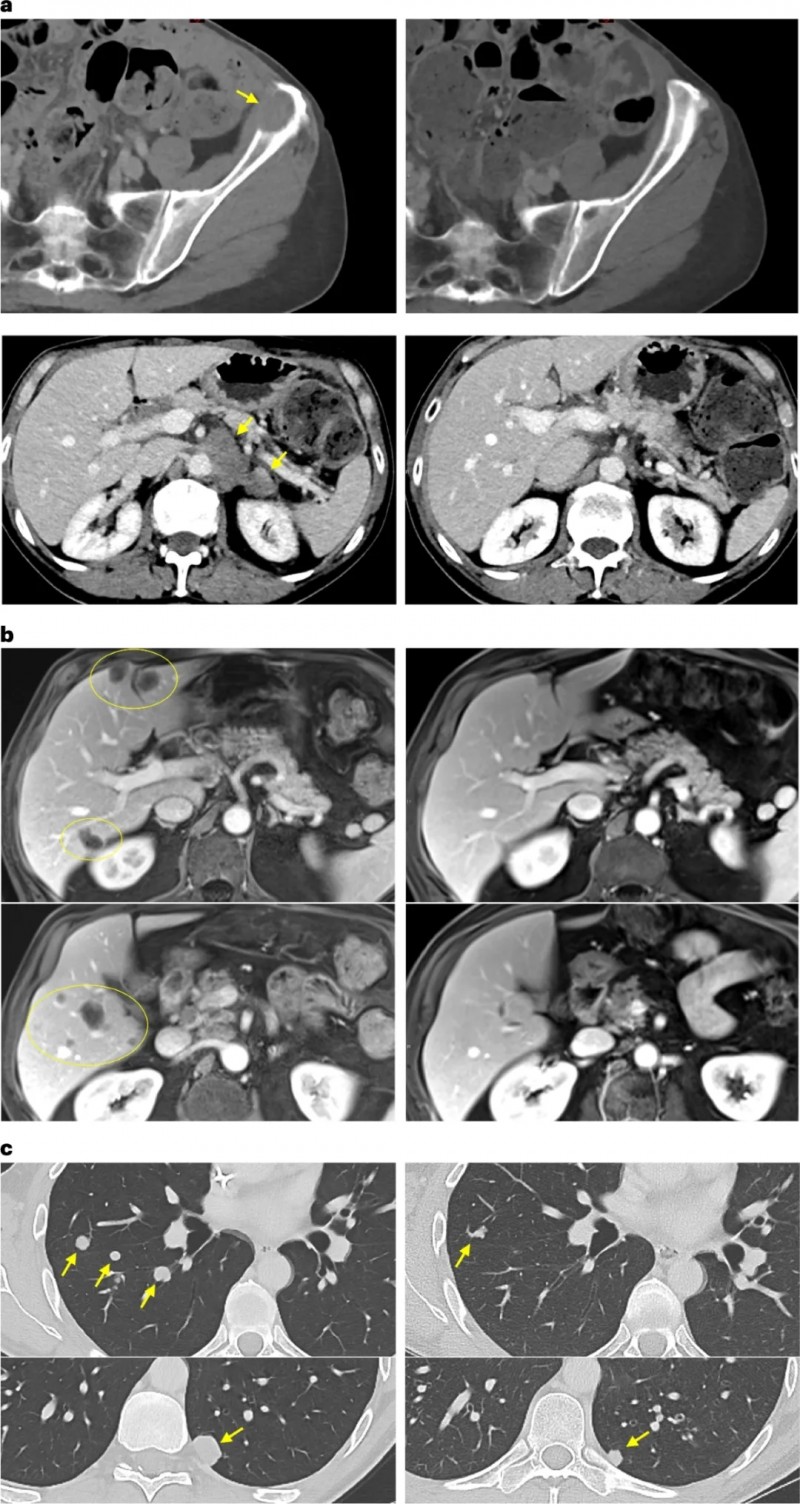

结果显示,总体患者根据严格的医学影像学标准(RECIST),确认的部分缓解率达到了15.1%。在联合了免疫检查点抑制剂(帕博利珠单抗)后,客观缓解率直接飙升至23.5%!

数据可能是冰冷的,但背后的真实案例却让人热血沸腾:

在随访中,有一位患有胰腺癌(被称为癌症之王,致死率极高)且已经转移至肝脏、淋巴结和腹膜的晚期患者。在接受了特定的TIL疗法联合治疗仅仅7个月后,他体内的1个肝转移病灶完全凭空消失,全身整体肿瘤面积大幅缩小了44.1%!

更令人拍案叫绝的是另一位胰腺癌晚期患者,在接受TIL回输后的仅仅6周内,影像学检查震惊了所有的主治医生——他肝脏上密密麻麻的数十个转移瘤,竟然不可思议地全部完全消退!